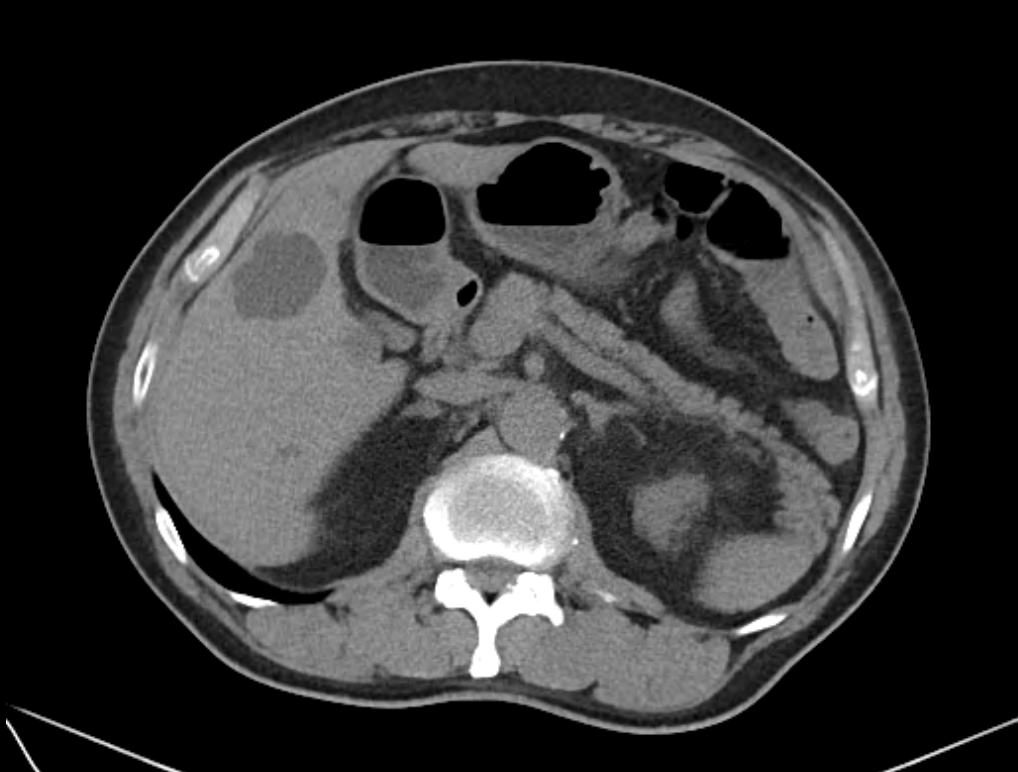

2) 복부 CT

CT는 낭종의 위치나 주변 조직과의 관계를 좀 더 정밀하게 평가할 수 있는 검사입니다. 복합낭종의 경우에는 CT 평가가 필요한 경우가 있습니다. CT는 검사할 때 방사선에 노출이 있기 때문에 필요한 경우에 사용하게 됩니다.